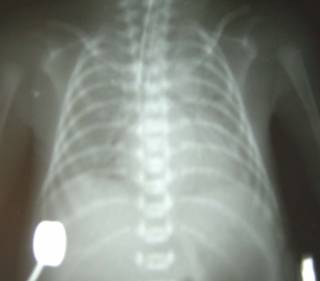

成人呼吸窘迫综合征